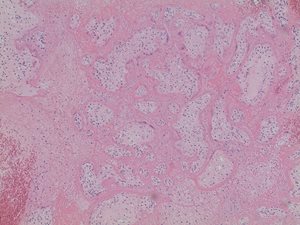

In both cases, placental histology showed extensive diffuse intervillous and perivillous fibrin deposition with widespread associated villous infarction and hemorrhage (Figs. 2a and 2b).

In addition, significant thrombi deep to the fetal surface and patchy hemorrhage throughout the placental parenchyma were identified in both patients (Figs. 2c and 2d). No acute or chronic inflammation was noted in either case.

Fig. 2c. Gross examination of the placenta reveals patchy hemorrhage throughout the placental parenchyma (Case 1).

Fig. 2d. Gross examination of the placenta reveals patchy hemorrhage throughout the placental parenchyma (Case 2).